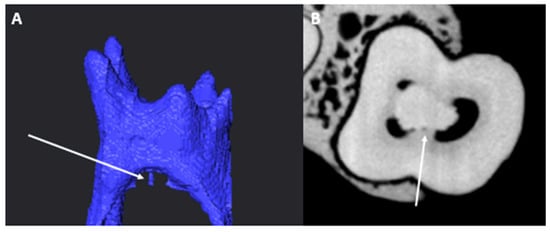

3.4. Chamber Canals